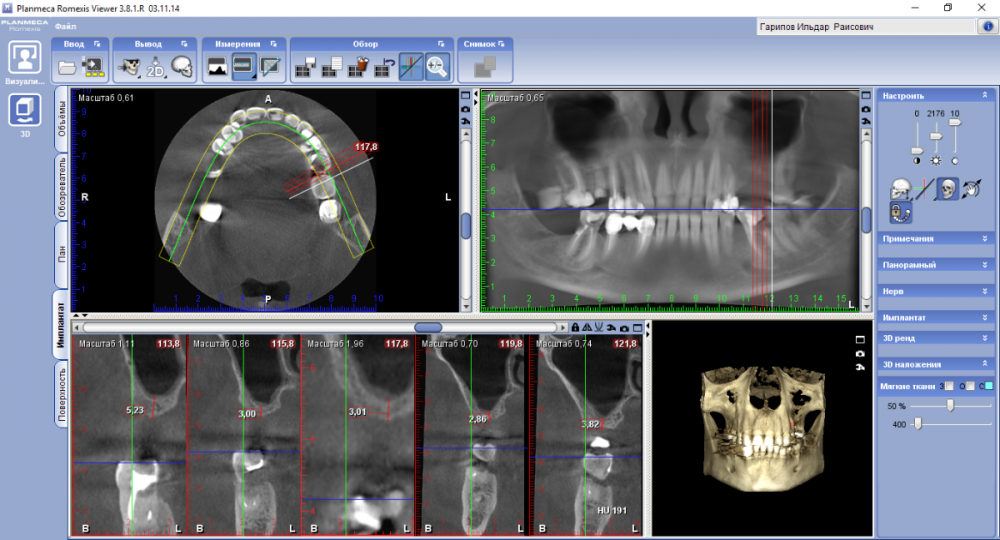

ДокторБро Опубликовано 9 ноября, 2021 Поделиться Опубликовано 9 ноября, 2021 Олег, прошу прощения за оффтоп, вроде это ваш сайт. Забыл старый пароль, на регистрацию ушло 30 мин. Ребусы у вас те еще. К вопросу -есть недостаток кости, 2 мм есть примерно. Если прикрутить к титановой сетке через заглушку, прирастет? Т.е. мы фиксируем имплант к кости, Если есть готовые решения - буду рад. Система NeoBioTech Ссылка на комментарий

ДокторБро Опубликовано 19 ноября, 2021 Автор Поделиться Опубликовано 19 ноября, 2021 (изменено) Пока так. К сожалению, в клинике нет КТ. Доступ через гребень. На деле оказалось 2мм кости. Будем ждать. Изменено 19 ноября, 2021 пользователем ДокторБро Ссылка на комментарий